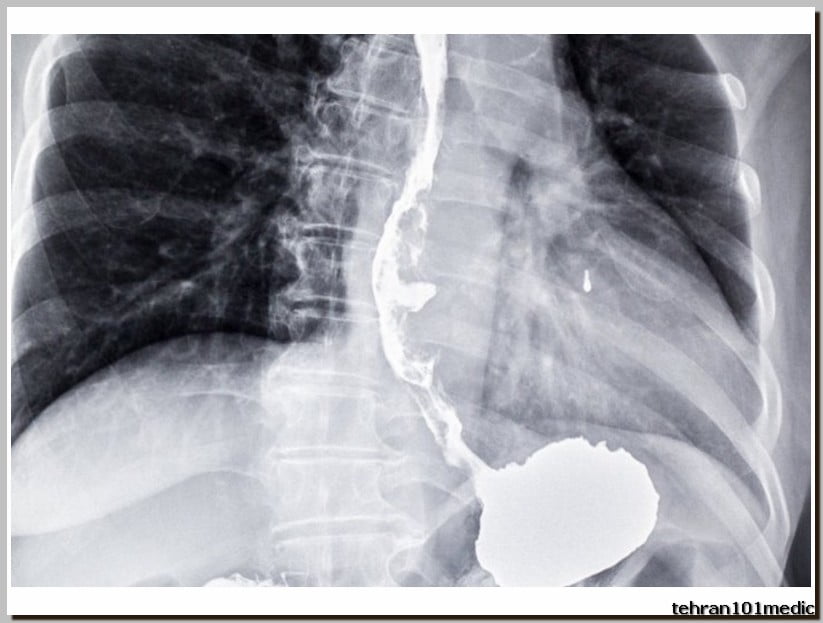

پرتونگاری مری یک روش تصویربرداری پزشکی است که با استفاده از پرتو X-ray انجام میشود. در این روش تشخیص، پزشک معالج تصاویری از داخل مری تهیه میکند. پرتونگاری مری معمولاً برای تشخیص مشکلات گوارشی و بلع مورد استفاده قرار میگیرد. کاربردهای پرتونگاری مری در تشخیص مشکلات گوارشی بسیار گسترده است به عنوان مثال، این روش ممکن است برای تشخیص زخمها، التهابها، تراکمات، تومورها، سنگها یا هر نوع نقص ساختاری دیگر در مری استفاده شود. بسیاری از پزشکان به دلیل دقت بالا و وجود خطای بسیار پایین در پرتونگاری، از این روش برای شناسایی و تشخیص بیماریهای مری، گوارشی و بلع استفاده میکنند. مشاهده تصاویر رادیولوژی از مری و دستگاه گوارشی به پزشک امکان بررسی دقیق محل بروز عارضه را میدهد.

- سرطان گوارش: از پرتونگاری یا رادیولوژی برای تشخیص سرطانهای گوارشی مانند سرطان معده، پانکراس، مری، کبد، کیسه صفرا، روده بزرگ استفاده میشود

این مجموعه مجهز به یکی ازکارامدترین انواع دستگاه های رادیولوژی دیجیتال و نرم افزارهای پردازش تصویر است که علاوه بر انجام تمامی آزمون های ساده رایج رادیولوژی، قابلیت انجام آزمون های تخصصی نظیر هیستروسالپینگو گرافی، بررسی دستگاه گوارش (باریوم میل ،سوالو، ترانزیت) و بررسی سیستم ادراری (IVP,VCUG,..) رادیوگرافی یکپارچه از کل ستون فقراتTotal Spine و Alignment view را دارا می باشد.